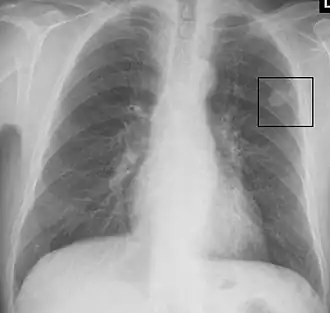

- Рентгенография, компьютерная томография, МРТ;